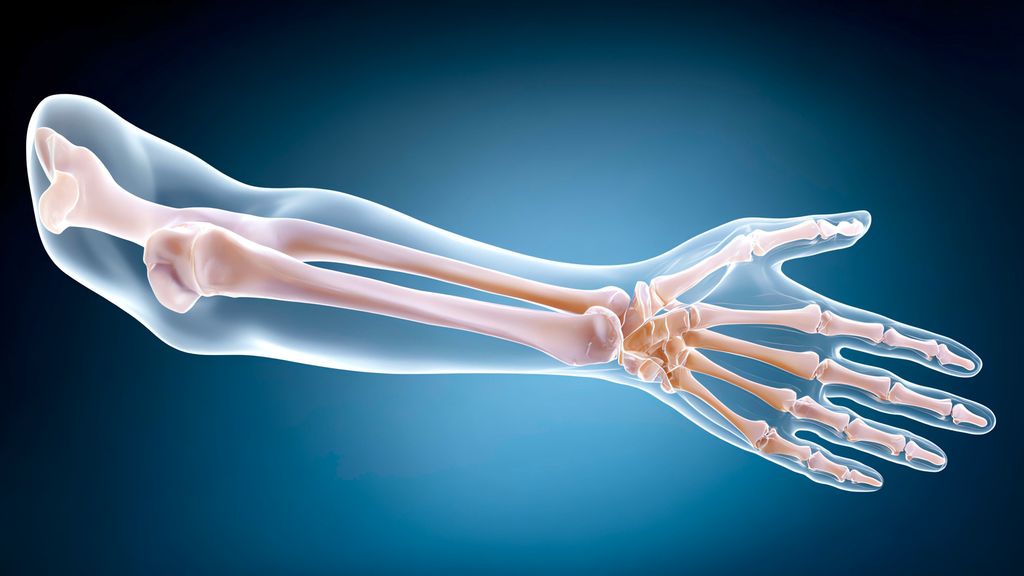

Als distale Radiusmalunion bezeichnet man eine in Fehlstellung konsolidierte distale Radiusfraktur. Je nach Ausprägung und funktionellem Patient:innenanspruch/-alter können diese von ...